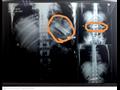

كشفت أشعة تلفزيونية أجراها مستشفى بنها الجامعي، اليوم الثلاثاء، عن وجود تليفون محمول بمعدة مريض، بلعه منذ فترة وصلت إلى 7 أشهر حتى الآن.

قال استشاري أورام الصدر وأستاذ جراحة القلب والصدر والمناظير بكلية الطب جامعة بنها، الدكتور محمد الجزار، إن المستشفى الجامعي استقبل المريض "ح. ر - 28 عامًا"، من مدينة كفر شكر بالقليوبية، اليوم الثلاثاء، حيث أجريت له أشعة تلفزيونية على الصدر والبطن، كشفت عن وجود تليفون بمعدته.

وأوضح الجزار، في تصريحات صحفية، أن المريض أكد أنه بلع التليفون منذ 7 أشهر على سبيل المداعبة مع أصدقائه، دون علم أسرته، موضحًا أنه بسؤاله عن سكوته طوال هذه الفترة، أكد أنه كان يظن أن التليفون سيخرج بمجرد حدوث استرجاع بالمعدة مرة أخرى، إلا أن هذا لم يحدث حتى الآن.

وأضاف أنه جرى تحويله إلى قسم الجراحة العامة بالمستشفى، وجرى إعداده حاليًا ووضعه بقائمة الجراحات، تمهيدًا لإجراء الجراحة سريعًا، واستخراج الهاتف.​